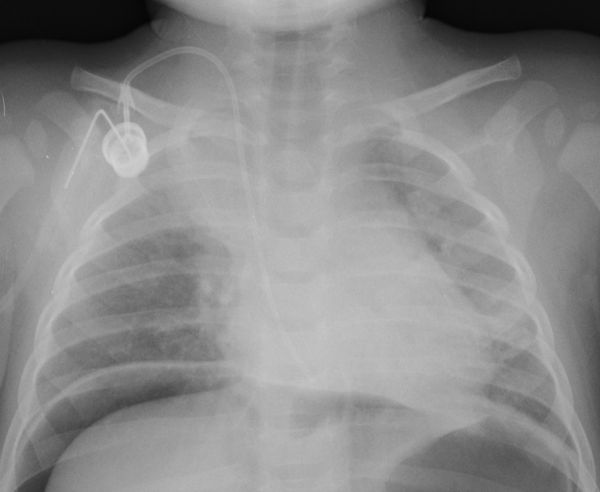

Neumoperitoneo en paciente oncológico de 15 meses.

En esta figura vemos cómo definimos el diafragma a ambos lados debido a la existencia de neumoperitoneo interpuesto entre este y el hígado. Por el mismo signo de la silueta definimos el reservorio de quimioterapia de densidad metal, superpuesto a densidades calcio, agua y aire.